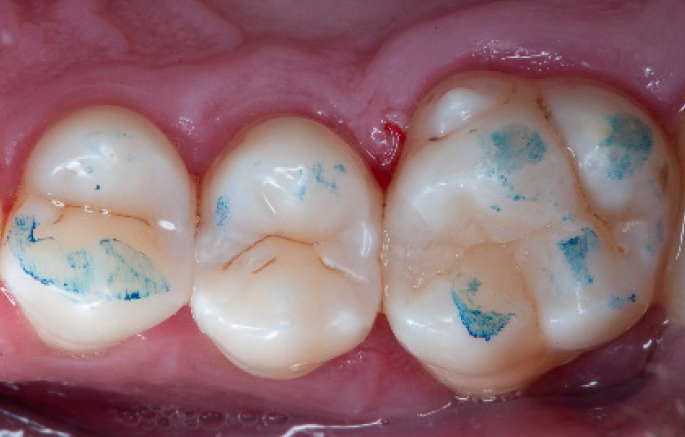

Selective enamel etching procedure with Conditioner2.

Step 7:

Adhesive application with a universal adhesive, Prime&Bond3.